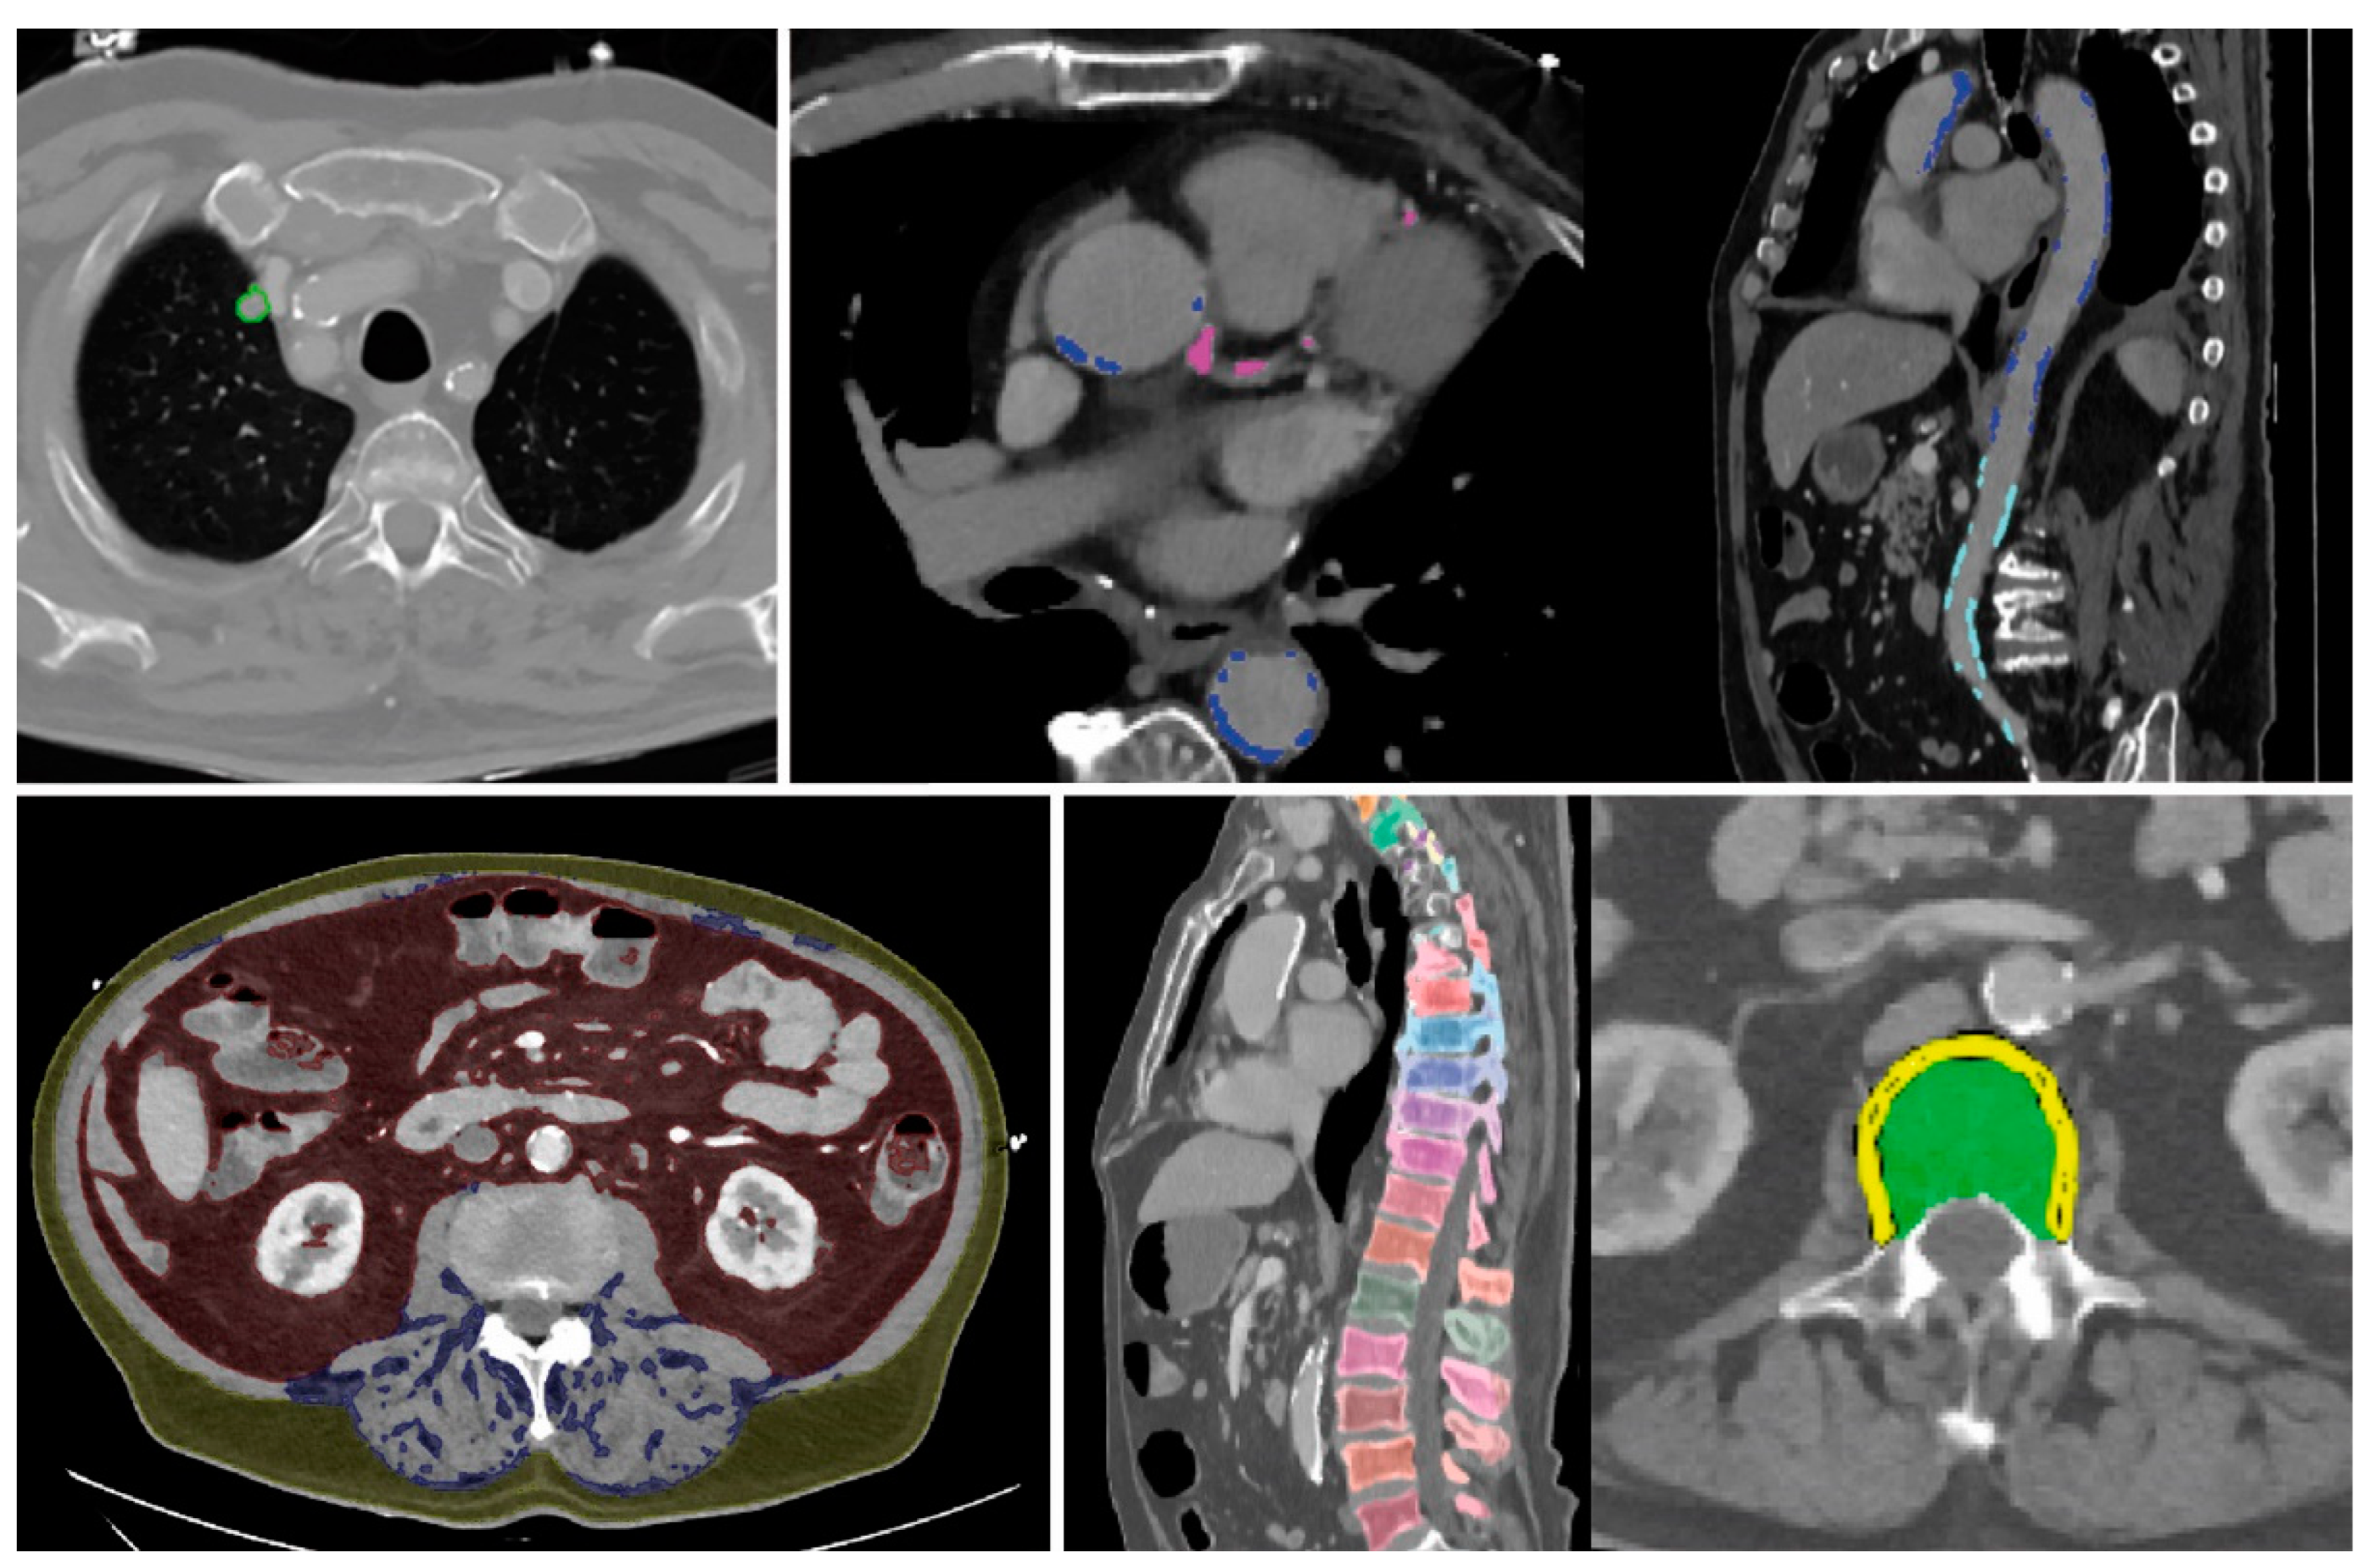

3.2.1. Example No. 1 ‘TAVI Patient’

3.2.2. Example No. 2 ‘COPD Patient’